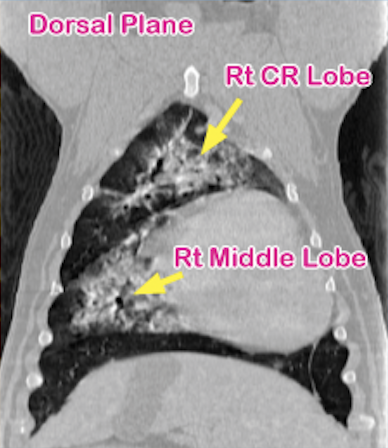

6-year-old American Bulldog with left-sided, muffled lung sounds received thorax CT scan to determine the cause.